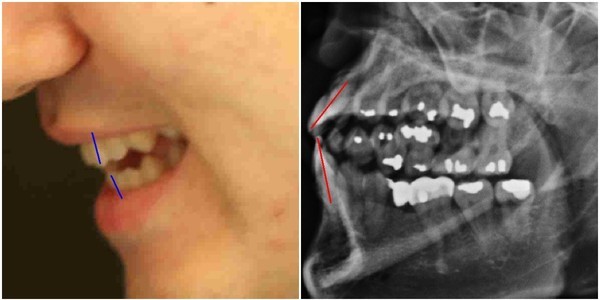

양승오 재판 피고인들은 이런 주장의 근거로, 박주신씨의 신체를 촬영한 것으로 알려진 엑스레이 판독결과 나타나는 의학적 차이점에 주목하고 있다.

-

- ▲ 양승오 박사와 치과의사 김우현씨 등, ‘박주신씨 병역비리 의혹’을 제기하고 있는 시민들이, 의혹을 뒷받침하는 근거 중 하나로 지목하고 있는 박주신씨의 치아가 보이는 엑스레이 사진. ⓒ 뉴데일리DB

주신씨의 치아가 보이는 엑스레이에서 드러나는 석연치 않은 의혹, 주신씨의 치아를 치료했다고 주장하는 전 참여연대 운영위 부위원장 출신 치과의사가 검찰에 제출한 증거자료에서 나타나는 ‘유령건강보험증’ 사용 내역, 주신씨 공개신검 당일 현장을 촬영한 서울시 직원의 동영상이 중요 부분에서 편집된 사실 등도, 이 사건 피고인들이 제시하고 있는 주요 증거들이다.

특히 피고인들은 국내외 전문의들이 박주신씨 명의의 엑스레이 판독결과, “동일인으로 보기 힘들다”는 의학적 소견을 밝히고 있다는 사실을 강조하고 있다.

지난 7월 양승오 박사 재판 3차 공판에 증인으로 출석한 세브란스병원 교수들도, ‘석회화 현상’과 ‘극상돌기 방향’에 대한 판독 결과, 박주신씨 명의의 자생병원 엑스레이와 공군훈련소 입소 당시 촬영된 엑스레이 사진이 다르다는 점을 인정했다. (※ 박주신씨 병역비리 의혹 핵심 증거인 3장의 엑스레이와 ‘석회화 현상’ 및 ‘극상돌기’에 대한 설명은 ‘편집자 주②’ 참조.)

- ▲ ▲ 박주신씨의 치아 상태를 알수 있는 엑스레이 사진 자료. ⓒ 뉴데일리DB

- ▲ ▲ 박주신 엑스레이(X-RAY)에 대한 치의학 박사의 분석자료. ⓒ 뉴데일리DB

양승오 박사 등에 대한 검찰의 수사가 진행되던 지난해, 이 사건 피고인들은 박주신씨 치아 X-Ray를 근거로, 박주신씨의 신체를 촬영했다는 X-Ray 속 피사체가 제3의 인물일 가능성을 주장했다.

주신씨의 치아 X-Ray는 허리 MRI 촬영 과정에서 찍힌 X-Ray 사진들 중에서 치아가 보이는 X-Ray 사진이다.

따라서 치아 X-Ray 상에 나타나는 각종 의혹은, 허리 MRI와 더불어 해당 피사체가 주신씨가 아닐 가능성에 무게를 더한다.

피고인들이 치아 X-Ray를 근거로, '피사체 바꿔치기' 의혹을 강하게 제기한 이유는, X-Ray에 나타난 치아의 상태가, 도저히 20대 중반 청년의 것이라고는 보기 힘든 특징을 갖고 있었기 때문이다.

주신씨 치아 X-Ray 사진을 보면, 치아 상태가 매우 불량하다는 사실을 알 수 있다. 치아 2개는 아예 없고, 아말감으로 때운 치아가 무려 14개에 달한다.

수은증기 방출 논란으로 문제가 되고 있는 아말감(Amalgam) 치료는 여러 가지 단점을 갖고 있어 사용빈도가 크게 줄고 있다는 것이 치과의료계의 공통된 평가다.

서울 방배동에 사는 중산층 청년이, 치과의사는 물론 환자들도 기피하는 아말감을 이용한 치과 치료를 이처럼 많이 받았다는 것은, 쉽게 받아들이기 어렵다는 것이 이들의 지적이다.

더욱 의심이 가는 부분은 주신씨의 경우, 하악 좌측 1소구치(아래쪽 좌측 첫 번째 작은 어금니)까지 아말감으로 치료했다는 사실이다.

이런 경우는 매우 드물다는 것이 치과의사들의 일반적인 견해다.

이 사건 피고인 중 한명인 치과의사 김우현씨는, 주신씨의 영구치가 맹출을 시작했을 것으로 추정되는 1990년대 중반 이후, 젊은 사람이 1소구치들을 포함한 구치부 치아 전체를 아말감으로 치료했다고 보기엔 무리가 있다고 지적했다.

치의학 박사 C씨는 뉴데일리와 기자와의 인터뷰에서 “주신씨의 전체적인 치료 상태를 보면, 소위 말하는 '야매'로 했을 가능성이 높다”고 밝혔다.

“(주신씨의 것이라고 알려진 구외 X-Ray 사진을 보면) 최근 국내에서 교육받은 치과의사의 치료라고 생각할 수 없을 정도.”

“(주신씨 구외 X-Ray 사진 상의) 45번, 46번 보철치료 및 치아 상실 문제도 마찬가지다. 보철물로는 상당히 저렴한 비귀금속 합금을 사용한 것으로 보인다. 37번 치아는 아예 없는 상태로 방치하기도 했다.”

“박주신씨의 가정환경을 고려하면, 이런 치료를 받았을 가능성은 1%도 안 된다. 서울 방배동에 거주했던 중산층 이상의 가정에서는 흔치 않은 상황.”

주신씨의 치아 아말감 치료와 관련돼, 김우현씨는 “혹자는 아말감 치료를 10개 이상 한 게 무슨 대수냐? 하면서 무시하는 경향이 있지만, 이는 모든 인과관계와 사실들을 무시하려는 것”이라고 비판했다.주신씨의 치아 X-Ray 사진 상에 나타나는 의문들은, 양승오 박사 등이 주신씨의 병역비리 의혹을 제기하게 된 핵심 요인 중 하나였다.